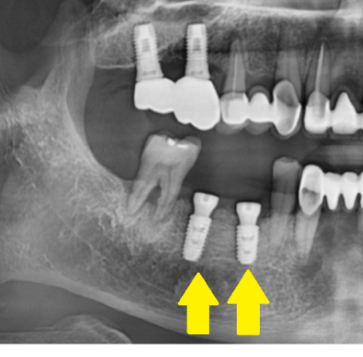

231023

엑스레이를 보면 이런 형태입니다.

임플란트 위에 작은 나사가 올라가있죠?

이게 힐링이에요

저는 작은 나사가 없어요!

없을 수 있습니다.

231109

위에 환자분은 임플란트만 심겨져있죠~?

잇몸뼈가 많이 부족한 환자분이였다면

임플란트를 잇몸 안에 쏘옥 묻어둡니다.